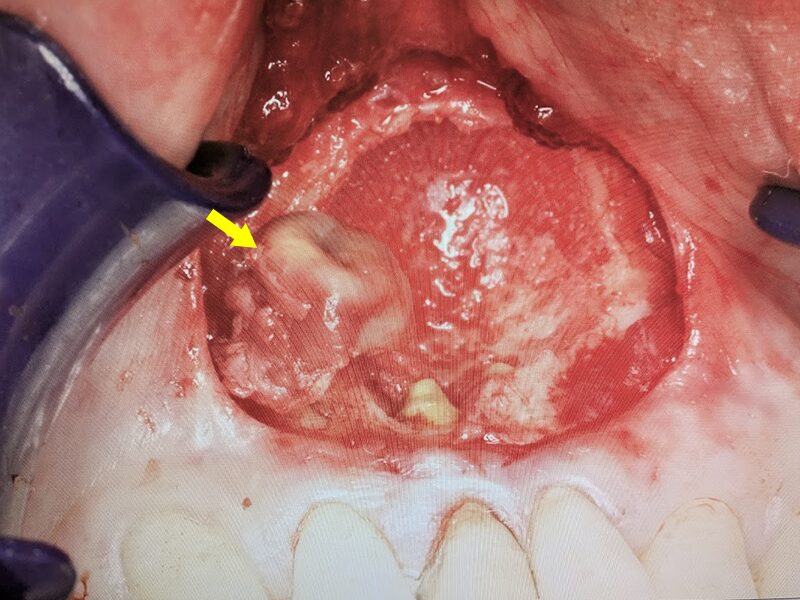

嚢胞壁を壊さないように骨から分離を行います。

骨内で嚢胞の剥離を進めます。

嚢胞を摘出します。

摘出された嚢胞です。